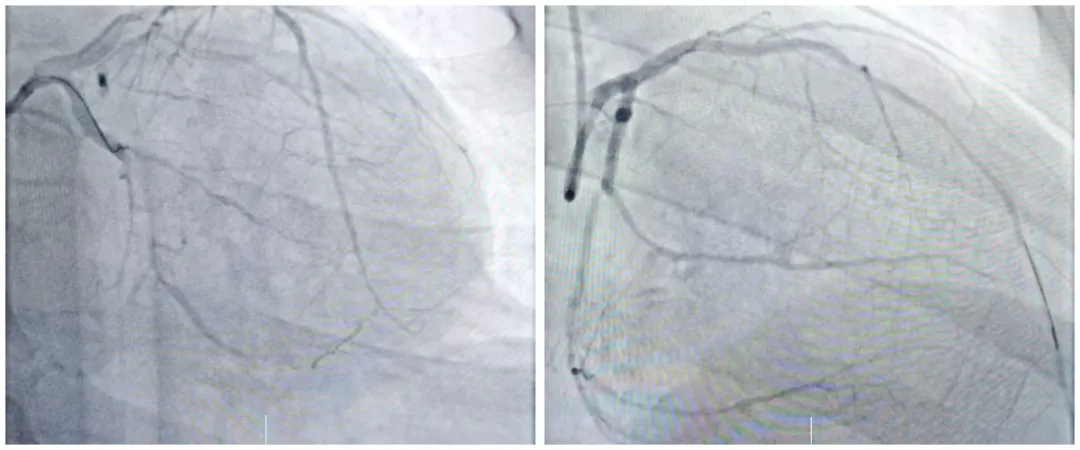

冠脉造影检查结果更是雪上加霜。检查显示,郑先生前降支近中段最重狭窄达95%,回旋支自中段完全闭塞,右冠脉全程弥漫性狭窄70%-95%,属于典型的高危复杂冠脉病变。更棘手的是,郑先生既往患有高血压、2型糖尿病,且血糖控制不佳,两个月前还曾因肺部感染接受抗感染治疗,多重基础疾病进一步增加了救治难度。

手术过程中,心血管内一科团队凭借丰富的介入经验与精湛的操作技术,在IABP的精准支持下,精准定位闭塞血管,小心翼翼地开通病变血管、植入支架。整个手术在患者清醒状态下进行,仅用时43分钟,便成功开通回旋支完全闭塞病变及右冠脉弥漫性重度狭窄病变,顺利完成血运重建。术后,郑先生的恢复情况超出预期,胸闷、气短等不适症状显著缓解,心衰指标大幅下降,受损的肾功能也逐渐恢复正常。目前,郑先生生命体征已趋于平稳,已顺利出院,逐步回归正常生活。